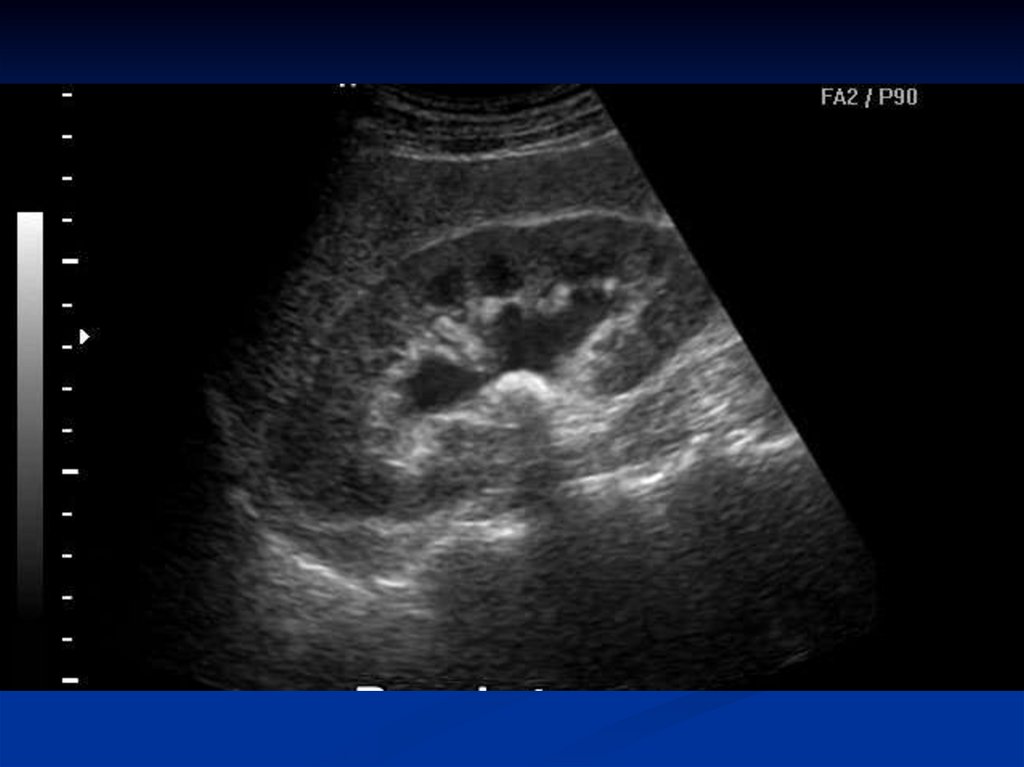

УЗИ почек и мочевого пузыря. Его преимущества неоспоримы:

• высокая информативность: определять параметры, количество, расположение (в мочеточнике, почечных лоханках, чашечках), а также оценивать состояние почечной ткани и наличие симптомов затрудненного мочеотделения (гидронефроз).

Что может увидеть врач на мониторе?

Эхогенные включения

Камни в почках на УЗИ смотрятся как белые (гиперэхогенные) кристаллы с эффектом акустической эхотени позади себя. Размер и форма включения также оцениваются.

Состояние почечной паренхимы

Оценить толщину и структуру почечной ткани, выявить возможные воспалительные изменения или рубцы

Расширение чашечно-лоханочной системы (гидронефроз)

При наличии камня, блокирующего отток мочи, чашечки и лоханки почки расширяются, что также видно на мониторе. Это является важным признаком, указывающим на необходимость вмешательства.

Состояние мочевого пузыря

Видны микролиты, а также остаточный объем после мочеиспускания

Несмотря на высокую информативность, УЗИ имеет некоторые ограничения. Микролиты, расположенные в узких участках мочеточника или за костными структурами, будут менее заметны. В таких случаях потребуются доп.исследования.